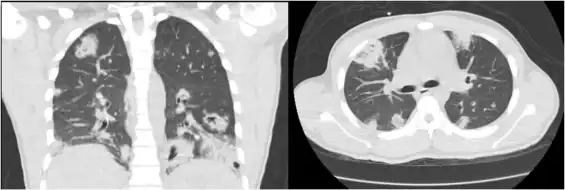

CT chest shows multifocal cavitary lung lesions[5]